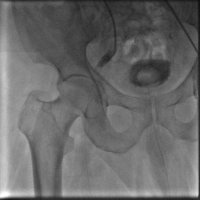

Yürürken bacak ağrısı olan ve ayak parmaklarında iyileşmeyen yaraları olan hastanın yapılan tetkiklerinde bacak damarlarının diz üstü ve diz altı tıkalı olduğu tespit edildi.Anjio da balon ve stent işlemiyle damarları açıldı. Hastamız şu an sağlıklı bir şekilde hayatına devam etmektedir.